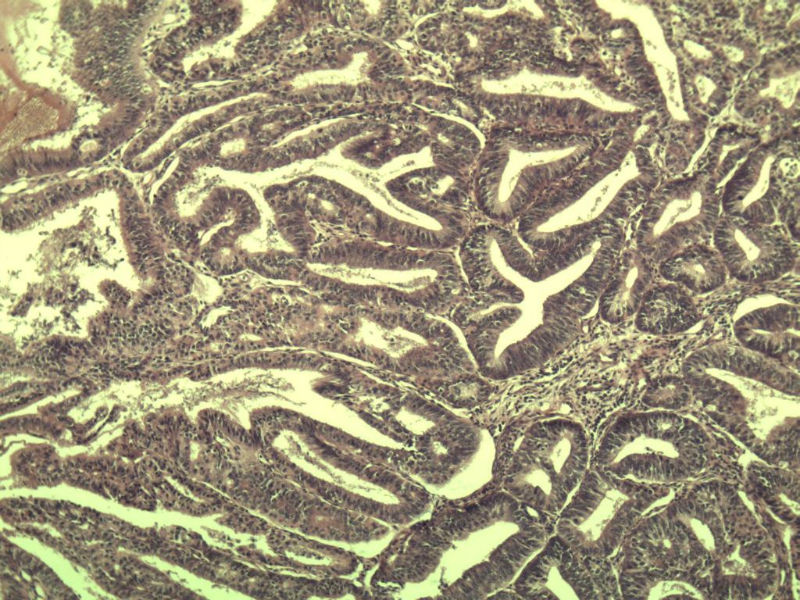

女 32岁 不规则阴道流血 一年  请各位老师看看 谢谢了

遵义医学院附属医院会诊结果    "复杂性增生伴非典型性 "

补充一下病史 病人10个月前因月经不规则行诊刮 诊断非典型性增生  上了曼月乐避孕环(好像是缓慢释放孕激素的那种),         都用激素治疗大半年了 还是这个样子 我还是觉得是癌  只有追踪一下以后病人的情况吧

高分化子宫内膜样癌

非典型复杂性子宫内膜增生,应了解雌孕激素情况。

子宫内膜复杂性非典型性增生,局灶区间质肉芽样(图5)及蜕膜样变,不够癌,建议临床查激素水平并追踪。

从照片看,没看到浸润的地方,我考虑是子宫内膜重度不典型增生。